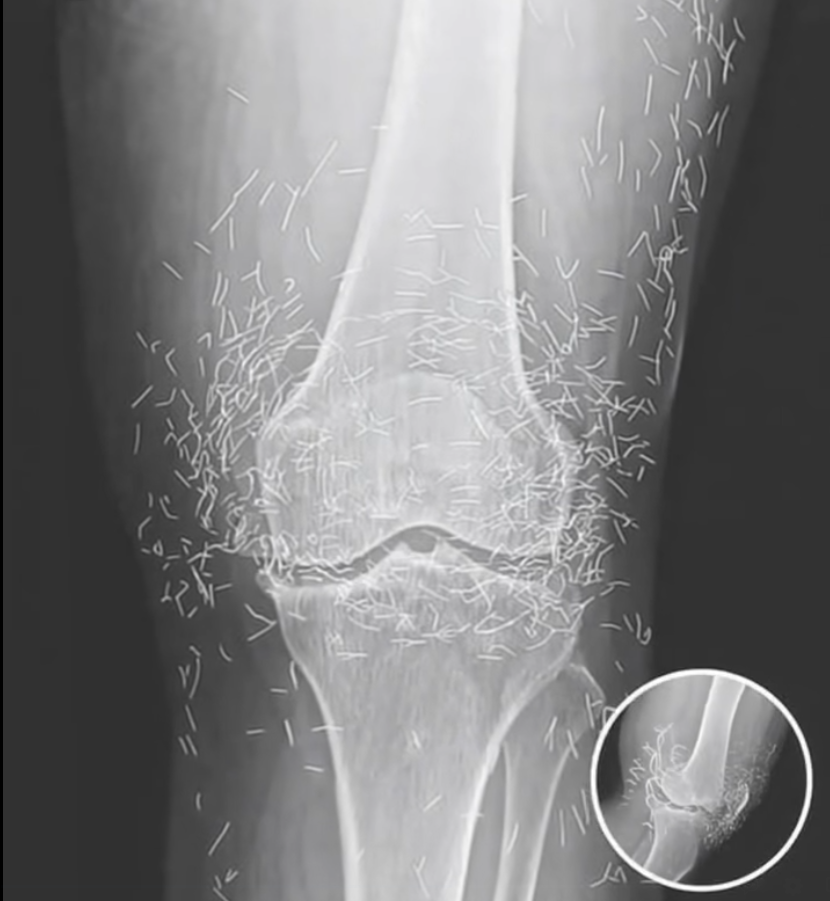

What started as a routine hospital visit for knee pain turned into a medical mystery that left doctors speechless. A 65-year-old woman in South Korea went in expecting a diagnosis of arthritis — but when her X-ray appeared on the screen, the room fell silent. Her knee joint wasn’t just worn down from age; it was filled with dozens of tiny gold needles. The strange discovery sparked immediate questions about how they got there and why they had remained unnoticed for so long.

The shocking X-ray served as a cautionary reminder of how alternative treatments can sometimes go too far. Specialists warn that leaving any metal object inside the body can cause inflammation, infection, and complications during imaging procedures. While acupuncture, when performed properly, is generally considered safe, experts emphasize that permanent implants are not medically approved or supported by evidence.